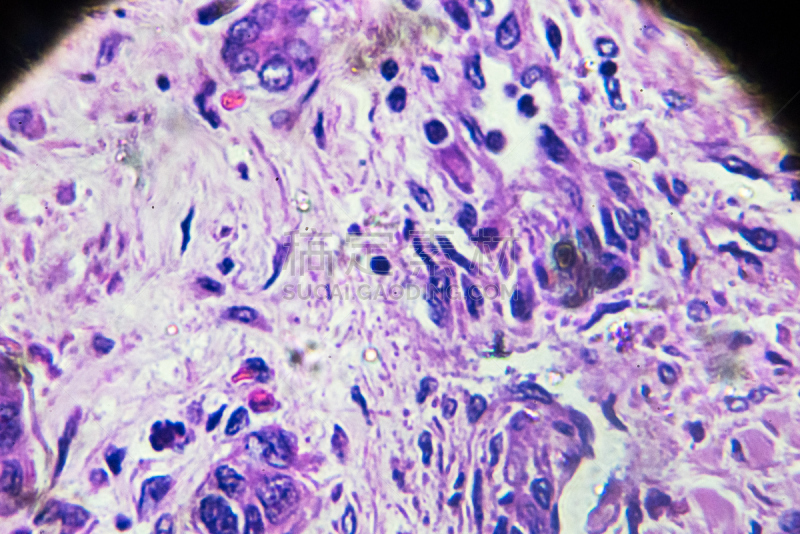

人类的肝脏解剖学详情

JPG